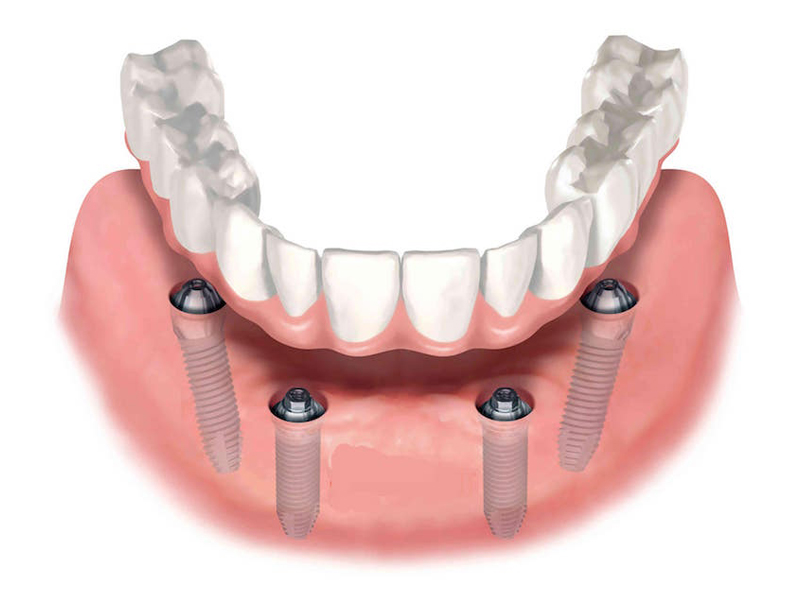

Implantology All on 4

This method is aimed both at edentulous patients who want a fixed prosthetic restoration, and at patients who have an insufficient amount of bone necessary to insert implants and are not candidates for conventional implant-prosthetic therapy.

Using the All-On – 4 method; Dental implants are inserted in the same day and in a few hours, a temporary but fixed prosthetic job is performed immediately which will remain until the implants are perfectly integrated into the bone. After about 4-6 months, definitive prosthetic rehabilitation will be performed, which will be screwed onto existing implants. The screw fixing will allow you to remove the restoration (fixed bridge) when necessary.

The specificity of this procedure is that the teeth are fixed on four implants. Thanks to the particular method of inserting the implants, bone reconstruction is not necessary, which is instead a requirement when it is necessary to reconstruct in patients who have total tooth loss.

The advantages of the all on 4 implant are:

minimum time spent in the dental clinic

short recovery period

absence of bone reconstruction

absence of the maxillary sinus lift and complex surgical procedures and represents a satisfactory aesthetic solution and allows correct oral hygiene maintenance.